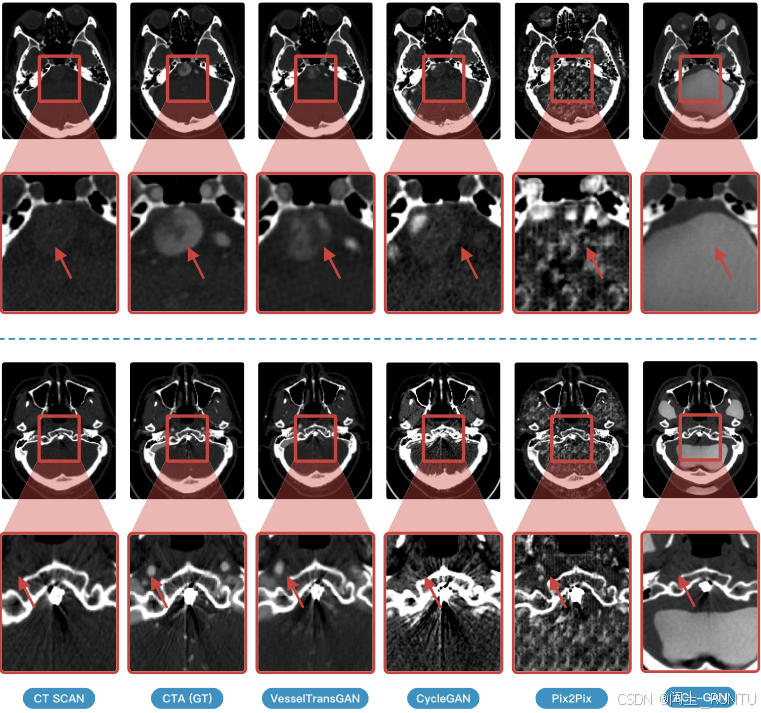

各个方法生成结果对比如下: